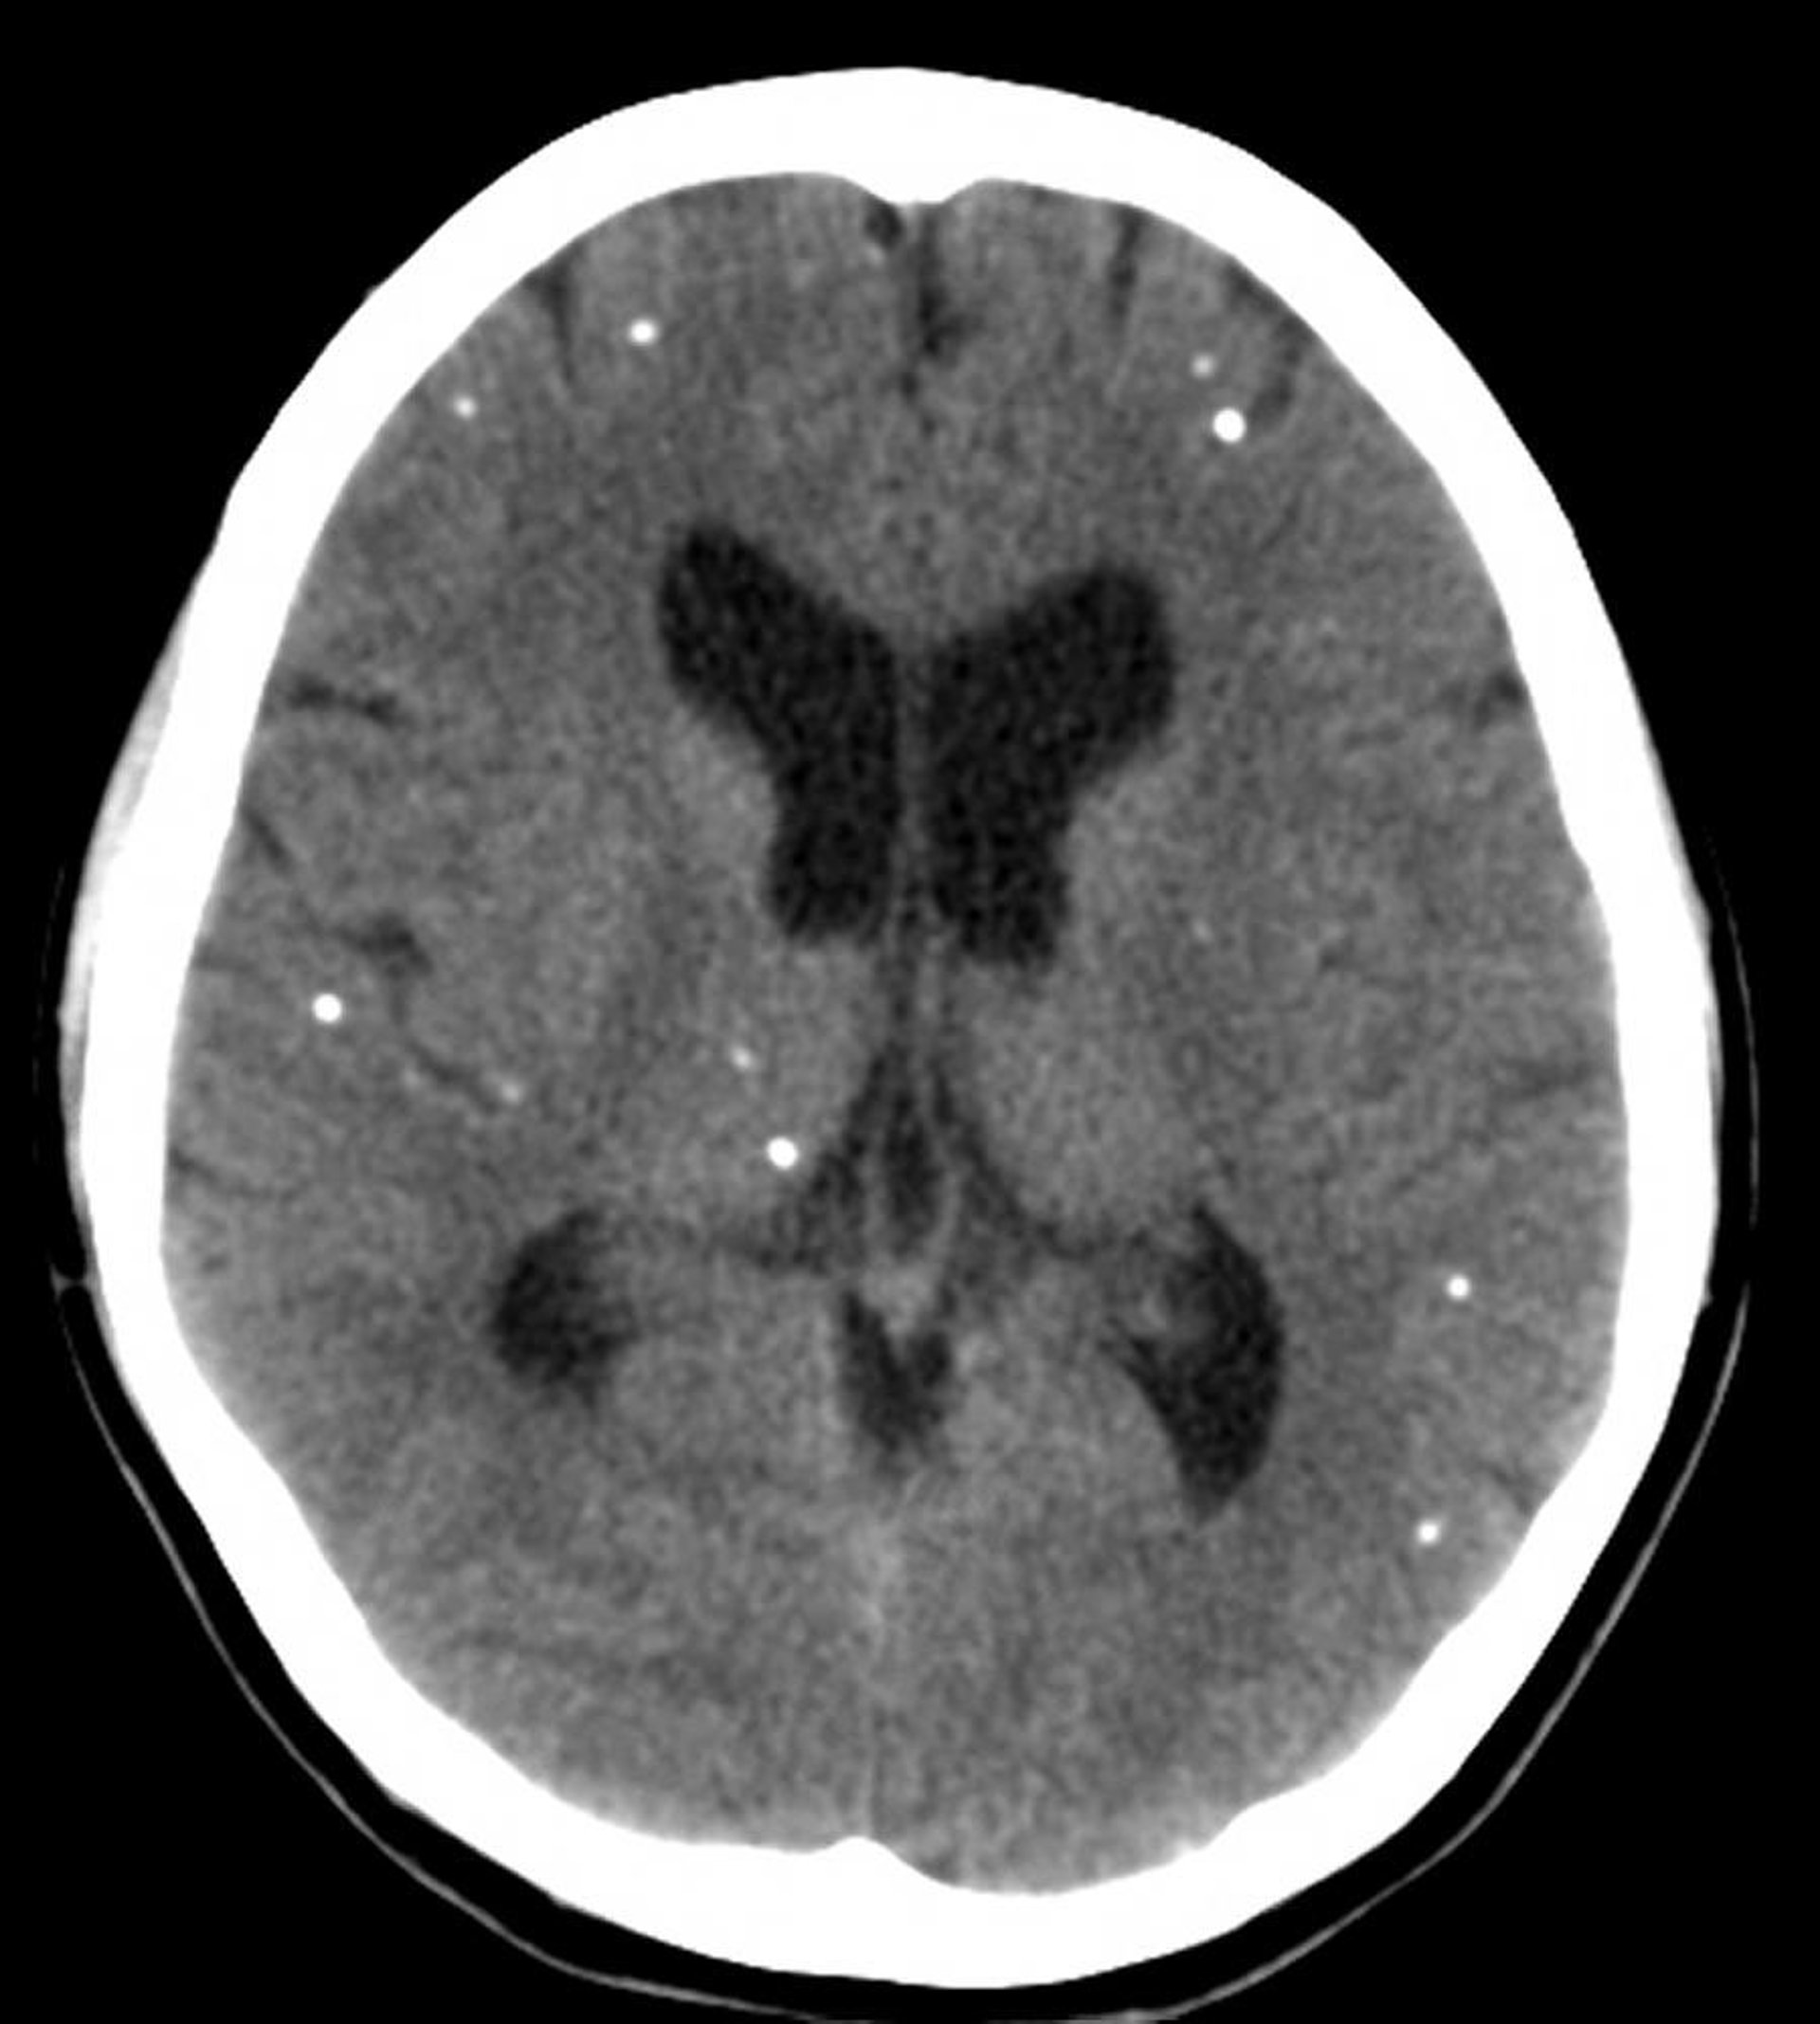

Нейроцистицеркоз

На этих снимках компьютерной томографии показаны множественные очаги кальцификации, представляющие кальцифицированные кисты у пациента с нейроцистицеркозом.

Courtesy of John E. Greenlee, MD.